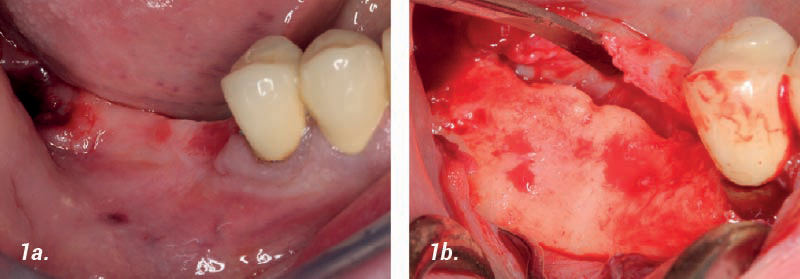

• 1a. Paciente desdentado distal en la cresta mandibular, se requiere colocación de implantes.

• 1b. La incisión del colgajo muestra una pérdida de altura y anchura de la cresta.